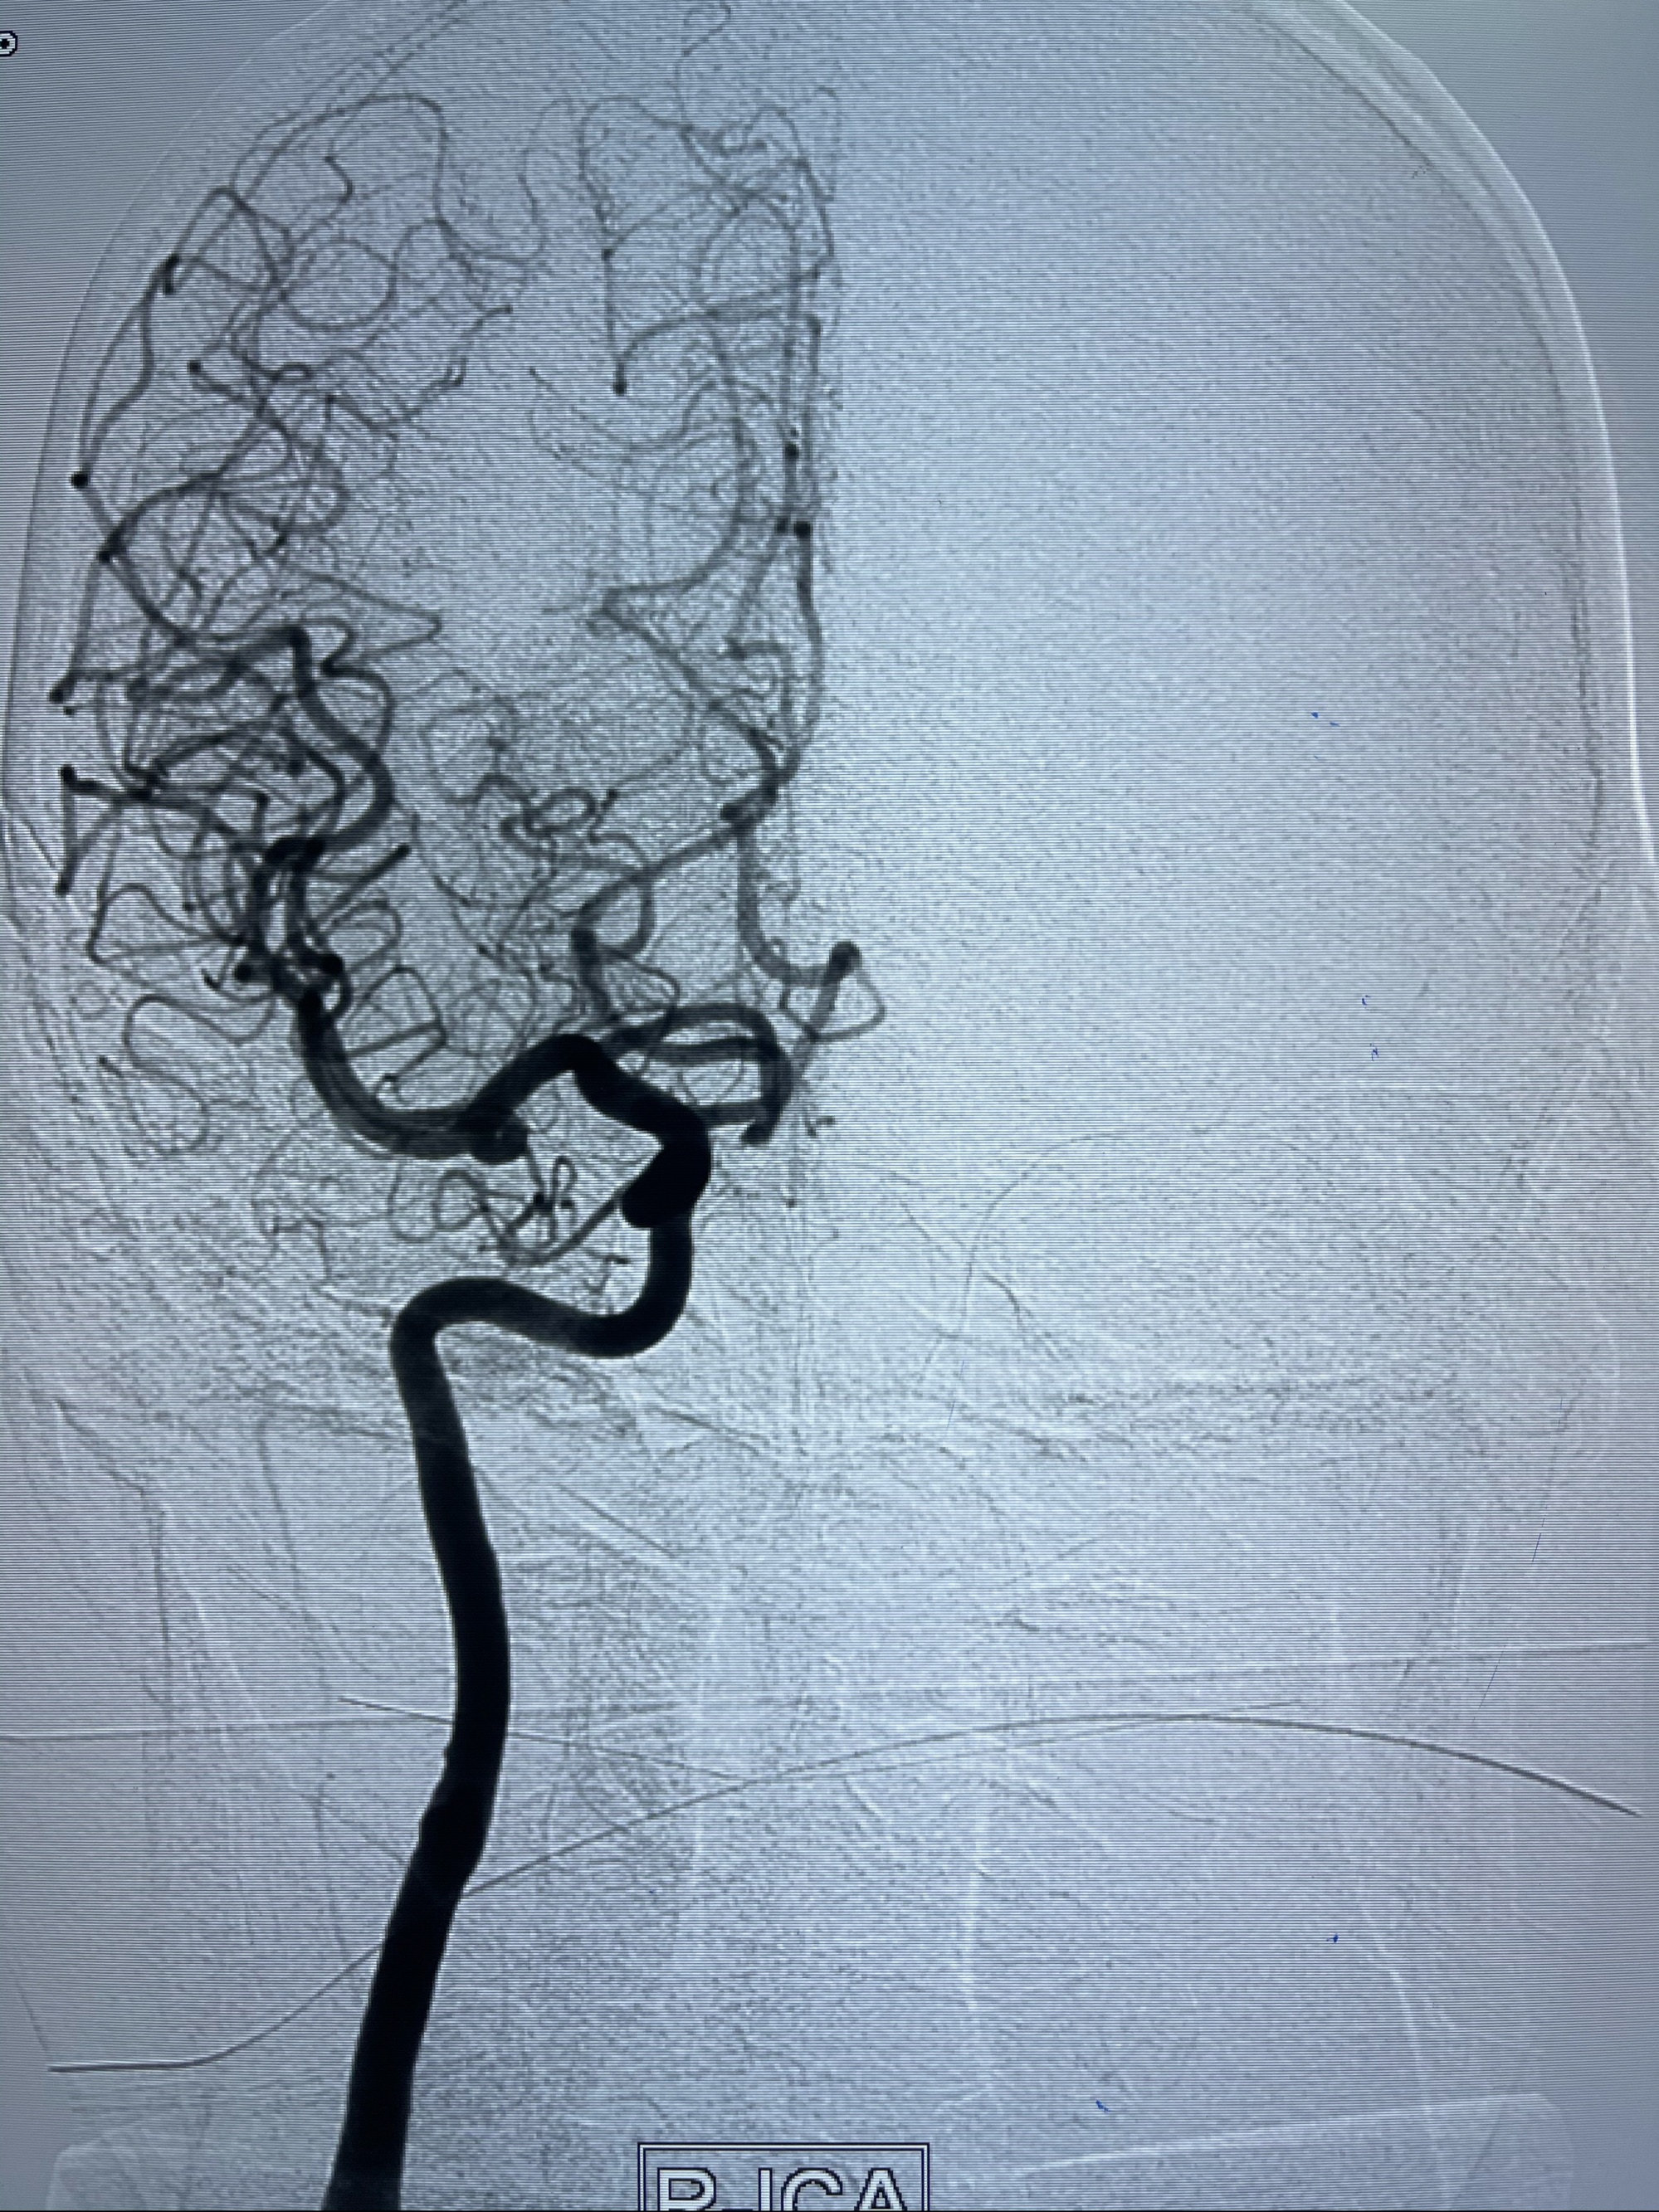

2021-03-08行全脑血管造影

1.右侧颈内动脉夹层动脉瘤Lvis支架辅助;

右侧颈内动脉夹层动脉瘤Lvis5.5-20mm支架辅助栓塞

即刻造影